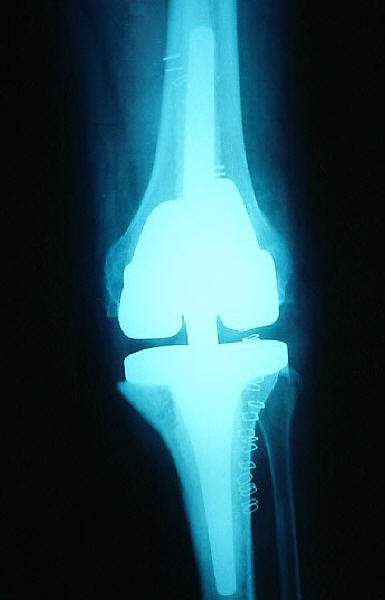

Prótesis completa de rodilla. Situación postquirúrgica.

Prótesis completa de rodilla. Situación postquirúrgica. Lateral.

Prótesis completa de rodilla.Lateral.

Prótesis completa de rodilla. Frontal.

Prótesis completa bilateral de rodillas.